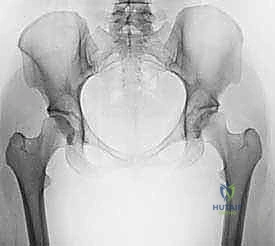

لفهم أهمية عملية قطع عظم الفخذ بين المدورين، يجب أولاً فهم تشريح مفصل الورك. يُصنف مفصل الورك كمفصل "كرة وتجويف" (Ball and Socket Joint). تتكون "الكرة" من رأس عظم الفخذ، بينما يتكون "التجويف" من التجويف الحقي (Acetabulum) في عظم الحوض.

تتصل الكرة ببقية عظم الفخذ عن طريق "عنق الفخذ". في الحالة الطبيعية للبالغين، يصنع عنق الفخذ زاوية مع جسم عظم الفخذ تتراوح عادة بين 125 إلى 135 درجة.

عندما تكون هذه الزاوية أكبر من الطبيعي (Coxa Valga) أو أصغر من الطبيعي (Coxa Vara)، يحدث خلل شديد في توزيع وزن الجسم على مفصل الورك. هذا الخلل يؤدي إلى تركيز الضغط على مساحة صغيرة جداً من الغضروف المفصلي، مما يسرع من تآكله ويؤدي إلى خشونة مبكرة (Osteoarthritis).

- خلل التنسج الوركي (Hip Dysplasia): حالة لا يغطي فيها التجويف الحقي رأس الفخذ بشكل كامل، مما يؤدي إلى عدم استقرار المفصل.